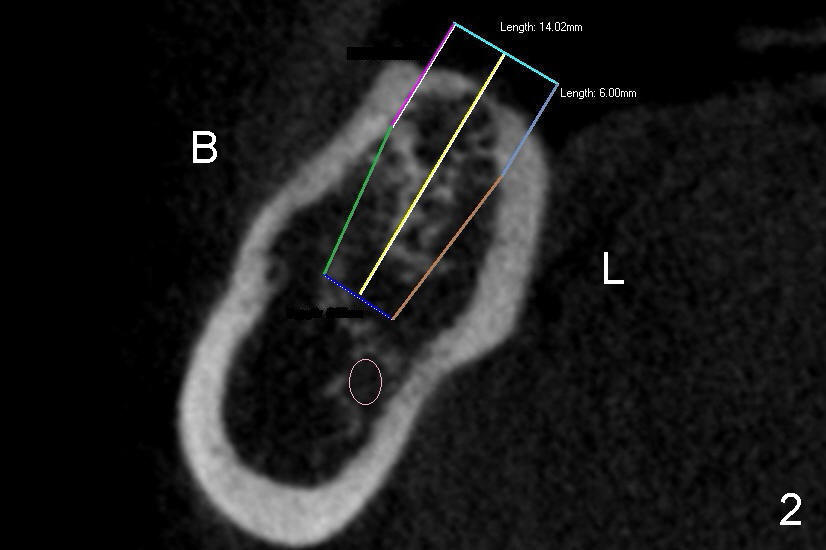

了解牙槽嵴颊舌侧宽度不外乎使用二医学到的望诊以及触诊,本例右下第一磨牙(6)缺牙区颊舌侧宽度相当可观(图一箭头之间),加上触诊,保险系数就不低了,本例不利因素是右下第二磨牙往近中倾斜(图一斜线),近远中间隙偏小。为了保险起见,我们做了CT检查,牙槽嵴横断面显示它的确很宽(图二:B:颊侧;L:舌侧),大约九毫米,我们准备植入直径六毫米植牙,植牙两旁还有一个毫米骨头,植牙成活就可能没问题。

CT扫描还可以准确定位下牙槽神经(图二:圆圈),由此我们初步决定了植牙长度:十四毫米(三个毫米在骨头外面,设计要求)。其实CT也不是那么重要,最重要还是术前术中拍摄准确X光片。